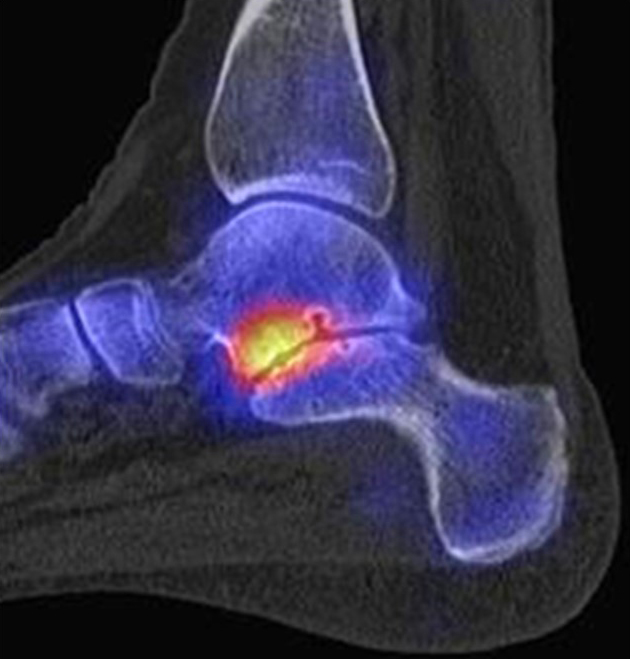

In Abbildung 3.4. ist ein typisches Beispiel für ein symptomatisches Os trigonum dargestellt.

Zum Lesen der Bildbeschreibung und zur Vollansicht bitte das Bild anklicken. Bild: H. C. Rischke